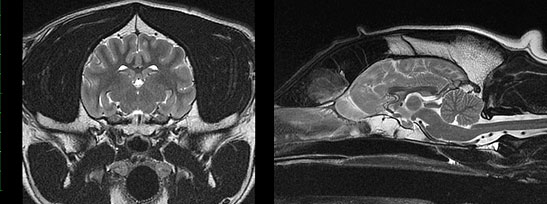

Fig 1: MRI scans of a dog with a normal brain

Fig 2: MRI scans of a dog with a brain tumour (shown as a white mass to the lower left hemisphere)